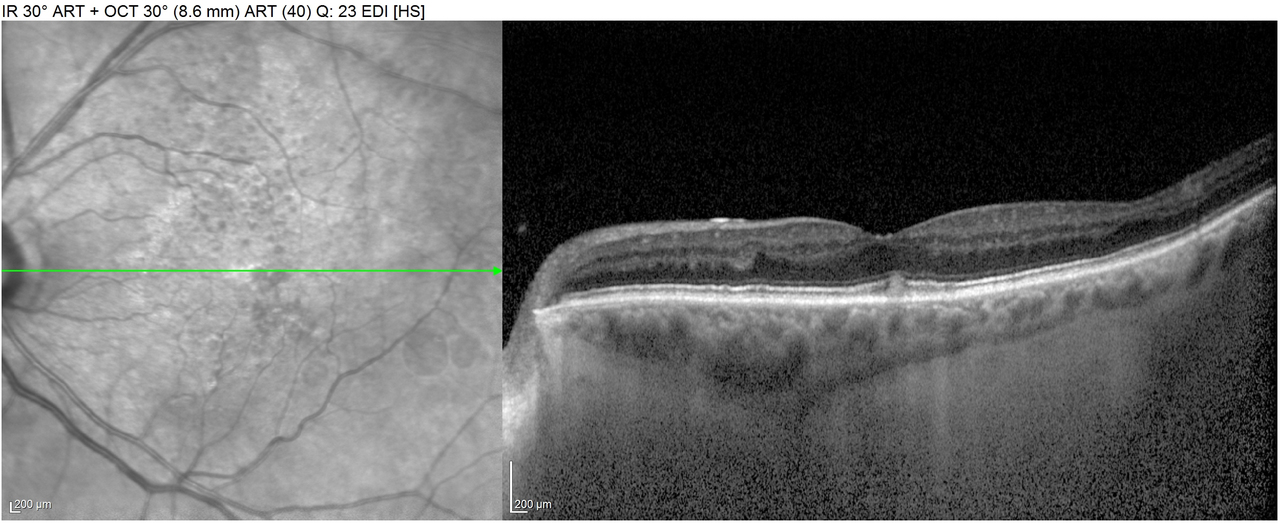

Voici les images des OCT maculaire DROIT

et GAUCHE

Question 5 : Quels signes sont présents sur ces deux OCT maculaire ?

Ici on remarque à DROITE une déformation dans l’épaisseur de la rétine qui correspond au décollement de l’épithélium pigmentaire (ou DEP). En effet le néo-vaisseau d’origine choroïdienne pousse la rétine vers le haut avant de saigner dans un espace anatomique appelé « espace sous rétinien », dont l’origine s’explique par l’embryologie oculaire (je vous renvoie vers vos cours de 2ième année de médecine). Ce soulèvement, qui est donc en dessous de la rétine, entraine un bombement vers le haut de l’épithélium pigmentaire d’où le terme « DEP ». Ensuite le sang de la DMLA exsudative se loge dans l’espace sous rétinien, d’où le terme de « liquide sous rétinien ». Ces signes sont très bien visibles ici. Sur l’œil GAUCHE, il n’y a ni DEP ni liquide sous rétinien, par contre on remarque que déformation rétrofovéolaire qui est en fait un drusen, la lésion AVANT le stade de DMLA.